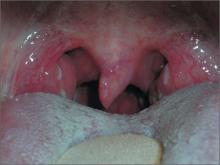

Dark area on tonsil

The family physician (FP) suspected strep pharyngitis, but decided to order a rapid strep test to confirm this impression. The test was positive.

The FP explained that the dark area on the tonsil was secondary to infection and would resolve over time. He also told the patient that the cobblestone pattern on the posterior pharynx may have been secondary to a history of allergic rhinitis or could have been newly acquired as part of the strep pharyngitis.

Posterior lymphoid hyperplasia is not a specific finding, even though it is commonly seen in allergic rhinitis and viral pharyngitis. Note, too, that patients may have strep pharyngitis even without tonsillar exudate.

In this case, the patient was given a course of penicillin VK for 10 days. The physician recommended oral analgesics/antipyretics as needed, plenty of fluids, and rest.